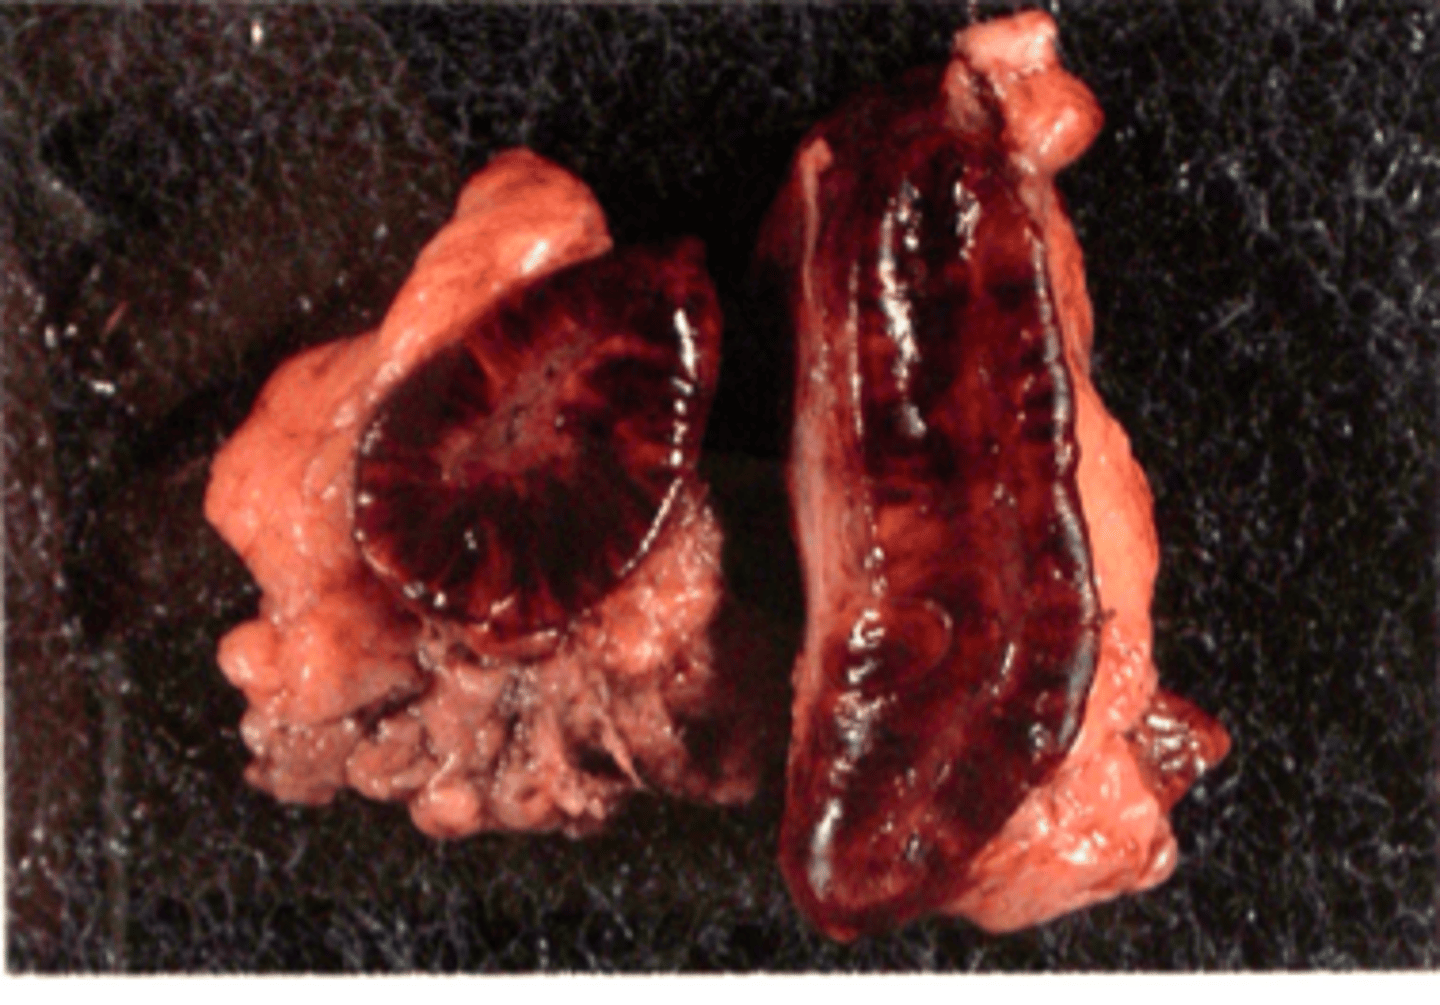

Benign hypofyseneoplasi med hæmorrhagi

Hovede fra hest, hvad er den patoanatomiske diagnose? Se pilen